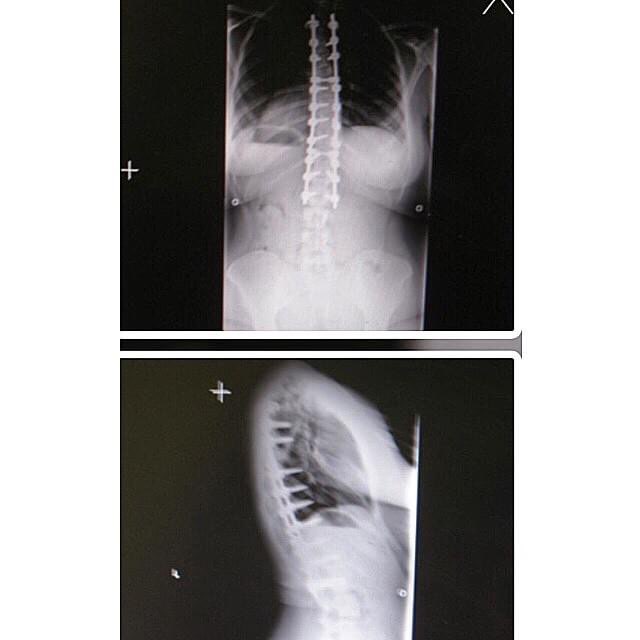

Somehow my spine’s anniversary always manages to pass me! 14 years! (Yes, I’m prepared to age myself😬) 🎉🥳🍾👏🏽 Some of you may know this, but this may surprise many. In June of 2010, at the age of 17 (and the summer before my senior year of high school), I underwent a spinal fusion from T-somewhere to L-somewhere else! 😂 For those in the know, this is the same surgery our dear friend and mailroom worker Eric had on his neck earlier this summer. It only really dawned on me this summer how absolutely massive and intense this surgery is; I mean your spine is second to maybe your brain? A tiny slip could ruin everything. I’m taking this time to celebrate Past Taylor who conquered this incredible physical feat! And to shoutout Troutman once again. Without FMLA, my mom would not have been able to “take the summer off” to be my nurse. Obviously hats go off to Bonnie, too!